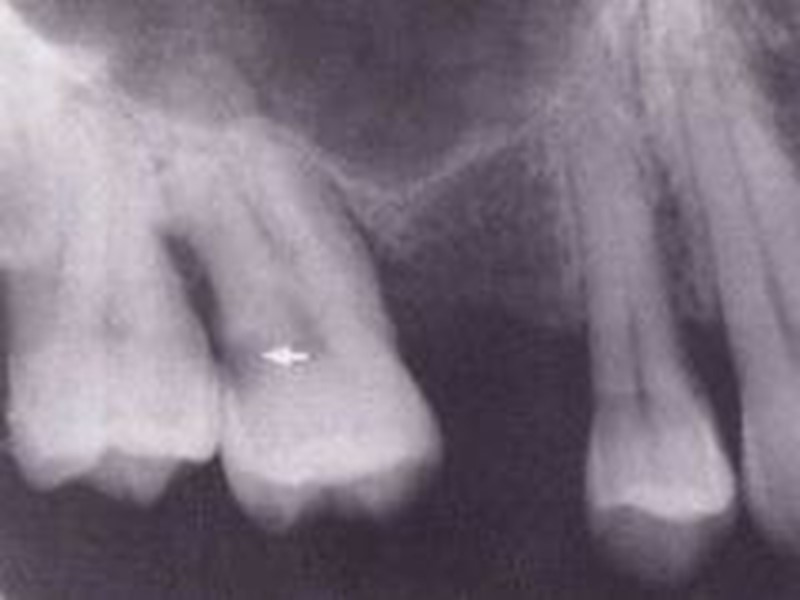

Дифференциальная диагностика поверхностного, среднего и глубокого кариеса Общее: 1. жалобы на боли от раздражителей, быстропроходящие после их устранения; 2. причина возникновения - зубная бляшка, локальное снижение рН; 3. возникает после прорезывания, содержание фтора в питьевой воде меньше 0,8-1 мг/л; 4. поражаются молочные и постоянные зубы; 5. прогрессирует, осложняется пульпитом и периодонтитом; 6. локализация, характерная для кариеса; 7. кариозная полость не сообщается с полостью зуба; 8. перкуссия безболезненна; 9. термодиагностика: возникает быстропроходящая боль на температурный раздражитель; 10. на рентгенограмме: кариозная полость не сообщается с полостью зуба, в периапикальных тканях изменений нет.